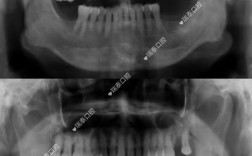

“植牙不能做CT”这一说法是完全错误的,植牙前不仅需要做CT检查,而且CT是植牙术前评估中不可或缺的关键步骤,植牙作为一种精密的外科手术,其成功与否依赖于对口腔内部解剖结构的精确掌握,而CT检查能够提供传统X光片无法比拟的三维影像信息,直接...

种牙前通常需要拍CT,这是确保种植手术成功、规避风险的关键步骤,虽然部分患者可能认为通过口腔检查或普通X光片即可评估种植条件,但CT的三维成像能提供普通检查无法企及的细节,直接影响种植方案的设计、手术的安全性和远期效果,以下从多个维度详细解...

种牙(种植牙)本身对进行CT检查没有直接影响,但种植体(特别是金属种植体)的存在会影响CT图像的质量,以下是详细解释:种植体对CT图像的主要影响:金属伪影原因:种植牙的种植体(植入牙槽骨的部分)通常由钛合金制成,这是一种高密度的金属材料,...

是的,种植牙前通常需要拍摄CT(锥形束CT,CBCT),这几乎是现代种植牙手术的标准流程和必要步骤,为什么种植牙前必须拍CT?主要原因如下:精确评估牙槽骨状况:骨量评估:CT能提供牙槽骨的三维立体图像,精确测量种植区域的骨高度、骨宽度、骨...

种植牙强烈建议拍CT,在绝大多数情况下是必要的,而不是“一定要”这个绝对化的词语,但可以说,在现代种植牙的标准流程中,CT检查已成为不可或缺的关键环节,以下是为什么CT对于种植牙如此重要的详细解释:精确评估骨量(高度、宽度、密度):核心问题...

种植牙后通常是可以做CT检查的,尤其是口腔专用的小视野锥形束CT(CBCT),“不能做CT”这个说法是不准确的,甚至可能是有害的误解,以下是详细的解释:📍1.为什么有人认为“不能做CT”?(误解来源)金属伪影:种植体(牙根部分)通常由...

种植牙本身通常不会完全阻止你做CT检查,但它确实可能对CT图像产生一定影响,主要表现为金属伪影,这种影响通常是可控的,并且经验丰富的医生通常能够识别并处理这些伪影,以下是详细的解释:金属伪影的产生原因:种植牙的种植体(植入牙槽骨的部分)通...